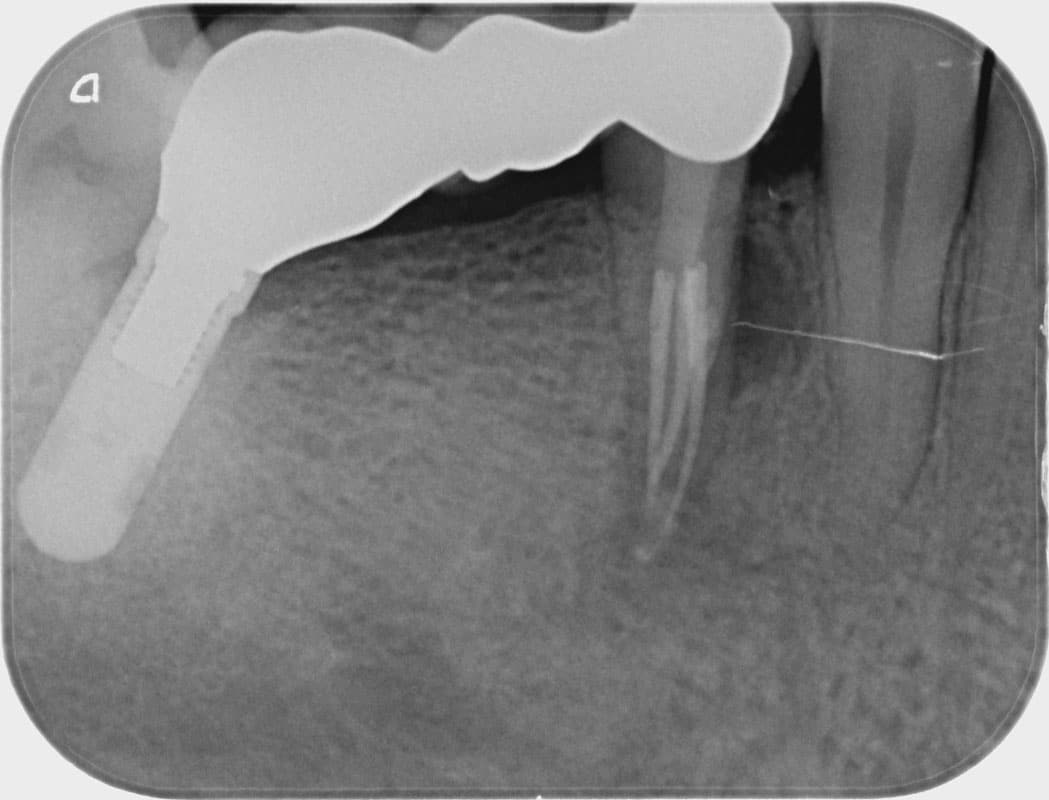

Radix entomolaris